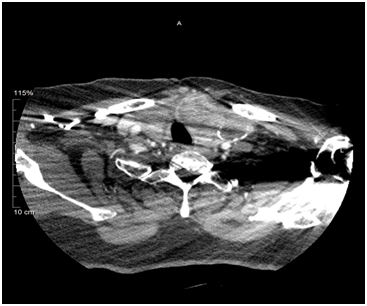

Thyroid cancers are the commonest cause of death among all the endocrine malignancies. Only 1 in 20 clinically detected thyroid nodules are malignant.2‒11 Several risk factors for malignant nodule have been identified (Table 1). Thyroid nodules under the age of 16 are highly likely to be papillary cancers. About 15 - 30% of CT PET positive nodules turn out to be malignant. Following are the US features suspicious for malignancy, which would definitely indicate FNAC: cells taller than wide in shape, cell with an irregular spiculated outline with a halo, presence of a hypoechogenicity in a solid nodule, micro calcifications and increased vascularity (Figure 1). Micro calcifications are thought to be due to superimposition of Psammoma bodies upon one another and are most suggestive of Papillary thyroid cancer and have a specificity of up to 95%.

Figure 1 US showing solid nodule with micro calcification and increased vascularity.